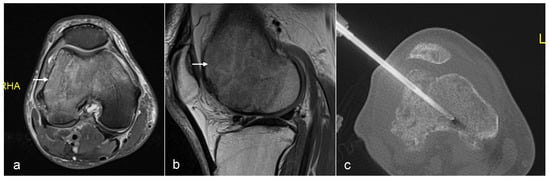

Figure 13. Axial CT (a) showing metastasis in the sacrum. Images (bd) showing sacroplasty with cement in both sacral ala.

3.5.2. Cement Augmentation

Cement augmentation is the injection of polymethylmethacrylate cement (PMMA) mixture into a bony defect to restore bony structural integrity and provide pain relief. The most common form is vertebroplasty in the context of vertebral compression fractures which—in the setting of oncology—include pathological fractures with underlying myeloma or metastases with resultant pain and disability refractory to conservative treatment. The procedure is also a useful adjunct following percutaneous ablation to restore structural integrity following bone destruction, particularly for larger lesions [33] (Figure 13 and Figure 14).

The most common type of cement augmentation at our centre is vertebroplasty. This is typically performed via a transpedicular approach into the lesion using an 11 G or 14 G bone biopsy needle system. Biopsy samples may be taken with the PMMA and then injected into the defect. A modified procedure is the kyphoplasty in which cement injection is preceded by the inflation of a balloon device in the vertebral body to create space with the cavity then filled with the cement. This is more effective in pain relief and minimises leakage but results in a longer and more expensive procedure [4,63].

Other variants with similar underlying principles include sacroplasty and acetabuloplasty. Complications to be aware of include cement leakage, which can lead to cement thrombosis, pulmonary emboli and compression of adjacent structures [64,65]. Nevertheless, cement augmentation generally remains a relatively safe and effective minimally invasive procedure, which can greatly improve patient quality of life in a palliative setting.